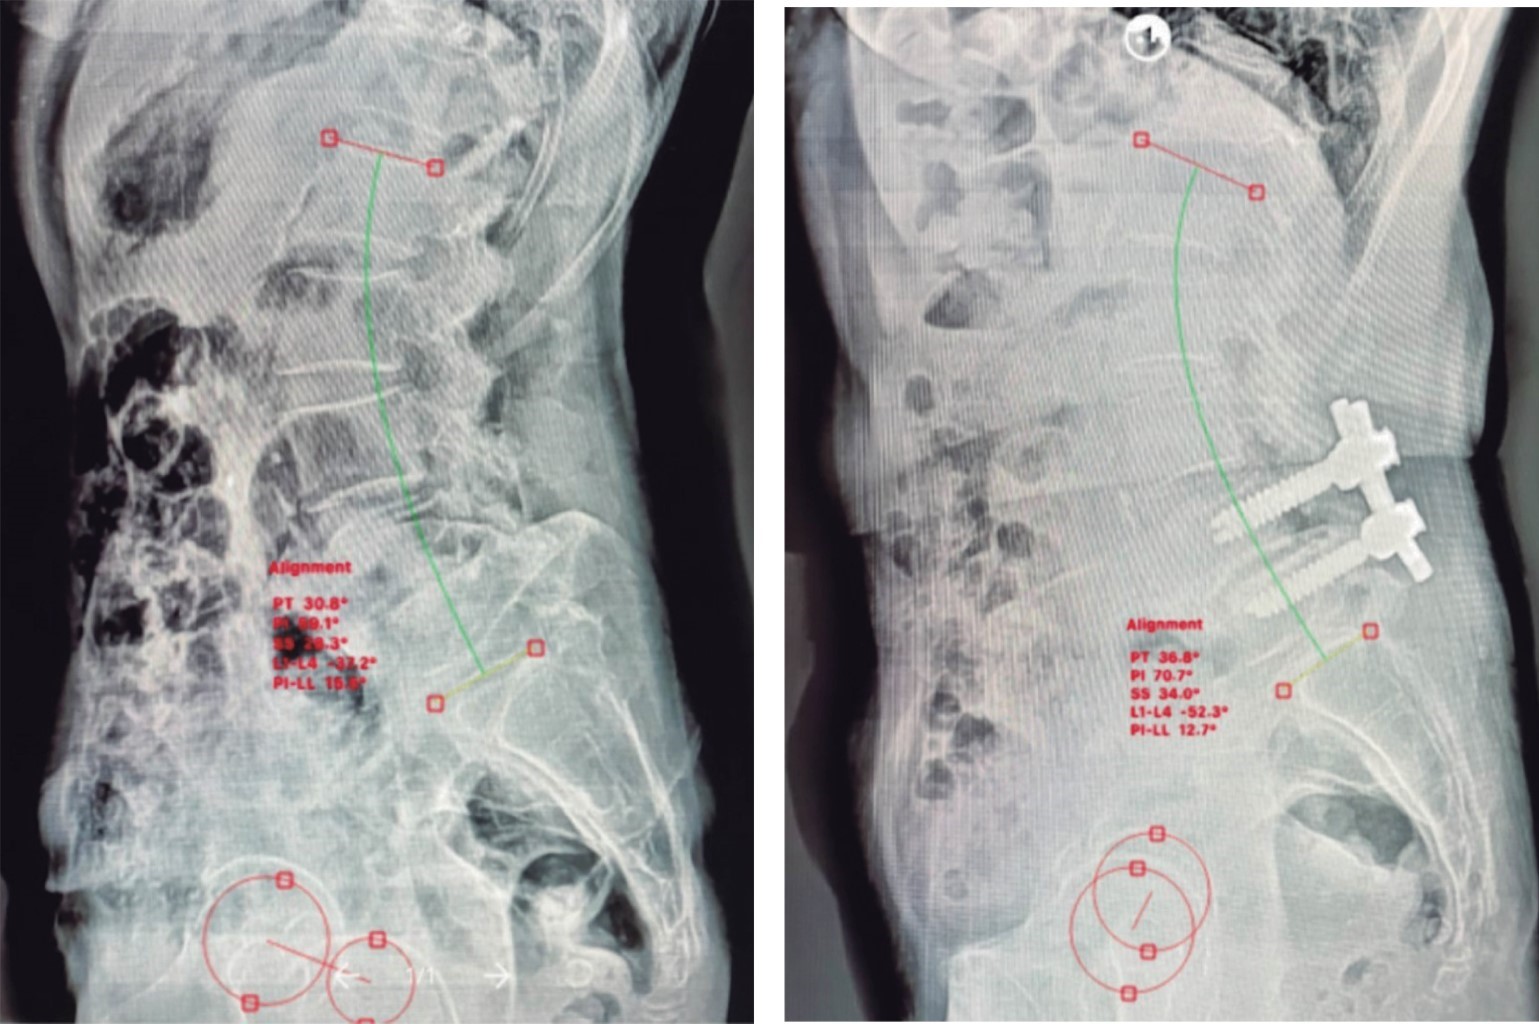

La propia bibliografía a veces no es clara si se trata de un conducto medular estrecho, espondilosis lumbar o sólo radiculopatía lumbar1 al hablar del síndrome cadera-columna y esto afecta la toma de decisiones, por ejemplo, durante el protocolo diagnóstico-terapéutico, una infiltración transforaminal de la raíz nerviosa que produce mejoría del dolor irradiado a la extremidad permite concluir que el dolor se origina en la columna. De otra forma, cuando se intenta una infiltración epidural, aunque tenga falta de respuesta, no se descarta que la fuente del dolor sea esta región y si respondiera no tiene efectos resolutivos a largo plazo. Estos estudios auxiliares básicos permiten distinguir qué zona es la causante de la sintomatología, propuestos desde Offierski, (las infiltraciones transforaminal y/o articular) y utilizados por otros autores. No son completamente sensibles o específicos, ya que tienen limitaciones como se mencionó previamente. En el caso de la cadera sólo se recomienda utilizar las infiltraciones cuando se encuentran datos de OA en rayos X y que la historia clínica y hallazgos de la exploración física sean sugestivos de patología de cadera ya que existe el riesgo de condrotoxicidad del anestésico local. En el caso de un paciente que no responda a la infiltración lumbar, se puede considerar la infiltración de la articulación para decidir cuál área atender primero, pero no existe todavía consenso o pruebas claras sobre qué área atender de forma prioritaria9,10 si ambas son fuentes de dolor aparentemente igual de importantes e incapacitantes. En todo paciente que se presente, aún con obvia sintomatología de la columna lumbar, se debe realizar exploración de las caderas para documentar el arco de movimiento y la presencia o no de dolor en las mismas. Particularmente, en todo candidato a fusión lumbar larga se le debe hacer la prueba de Thomas para evaluar la presencia de una contractura en flexión de la cadera. En el escenario originado en la patología de cadera, se deben explorar los probables signos y síntomas derivados de la columna lumbar. También en todo paciente con dolor del área lumbopélvica, aun cuando la historia clínica y exploración física pinten un cuadro claro y se tenga una buena impresión diagnóstica inicial, se debe siempre tomar estudios radiológicos completos. En ocasiones será suficiente con radiografías simples que incluyan pelvis con ambas caderas y columna, al menos la columna sacrolumbar completa para poder valorar los parámetros espino-pélvicos y cualquier dato radiográfico de osteoartritis degenerativa en caderas, columna lumbar y pelvis (Figura 3).8,20